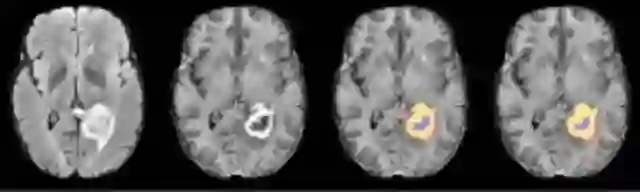

去医院看病不可避免的一件事情就是“拍片”,不同的科室、不同的检验方法会产生各种各样的医学片子,X光、CT、核磁、病理、B超、OCT、超声等等,这些片子必须由放射科或病理科的专业医师进行解读,患者往往要等上好几个小时才能拿到解析报告,而且准确度和医生的经验有很大的相关性。一个不争的事实是,我国医学影像误诊人数每年达到5700万,主要发生在基层医疗机构。我国医学影像数据量每年增长30%,而专业医师的增长率仅仅只有4.1%,巨大的缺口催生了急迫的需求。据调查,AI可将医生的看片时间平均减少4.25个小时,准确率提高到90%以上。

第一类公司是人工智能技术公司,提供智能影像分析系统,客户主要有医疗设备厂商、基层医疗机构、远程医疗平台等,代表公司有DeepCare、推想科技、图玛深维、雅森科技,成立时间一般较短。

第二类公司是医疗影像云服务商,近几年我国医学影像逐渐从传统胶片过渡到电子胶片,跨平台的影像云有巨大的市场需求。积累了足够多的数据后,这些公司正在切入到影像的智能分析,其中以汇医慧影、医众影像、医渡云为代表,成立时间一般为二到三年。

机器自动标记脑出血区域